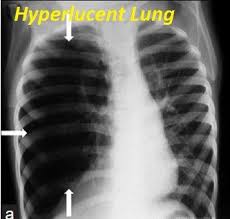

Hyperlucency x ray definition. The obstruction that leads to lobar emphysema typically causes dynamic hyperinflation which manifests radiographically as lobar hyperlucency and mediastinal shift on the chest x ray. Spirometery of the patient was within normal limits. Even in adults pulmonary hyperlucency can be caused by congenital and acquired conditions. Information and translations of lung hyperlucent in the most comprehensive dictionary definitions resource on the web.

Abstract pneumothorax is the most urgent cause of a hyperlucent thorax. The radiographic finding that a lung or portion thereof is less dense than normal as from air trapping by a bronchial foreign body asymmetric emphysema or decreasing blood flow. Emphysema causes both over inflation and decreased pulmonary vasculature. Asymmetrical distance between the medial.

Spirometery of the patient was within normal limits. The most common causes of pulmonary hyperlucency in adults are summarized in figure 1. Hyperlucent lungs result from air trapping or decreased pulmonary vasculature. Unilateral hyperlucent lung.

Contrast enhanced computed tomograph cect of the chest showed an unremarkable lung fields and vasculature. An understanding of the broad differential di agnosis of pulmonary hyperlucency is necessary to determine the underlying cause and provide appropriate patient care. Every unnecessary x ray in a woman of child bearing age represents a danger that should be weighed against the benefits. What does lung hyperlucent mean.